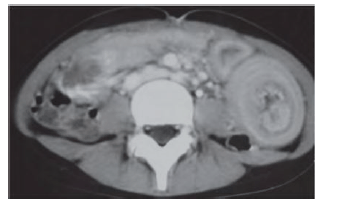

Menino de 14 anos de idade, com diagnóstico de púrpura de Henoch-Schönlein, procurou atendimento em uma emergência em razão de dor abdominal aguda de forte intensidade e vômitos há algumas horas, além de eliminação de fezes com muco e sangue. Realizou tomografia de abdome mostrada na figura apresentada.

A melhor hipótese diagnóstica para esse caso hipotético é de